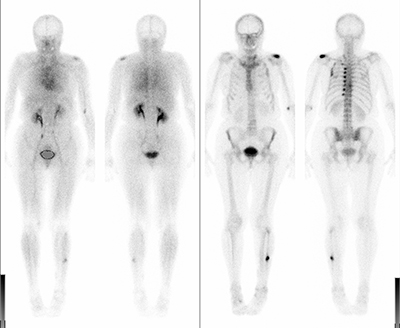

Multiple knöcherne Läsionen nach einem Fahrradsturz: Linkes Schultergelenk, Rippenserienfraktur, linkes Wadenbein. An den Frühaufnahmen (linkes Bild) stellen sich die frischen Herde mit verstärkter Durchblutung dar. Die Spätaufnahmen (rechtes Bild) dokumentieren den reparativ verstärkten Knochenstoffwechsel.